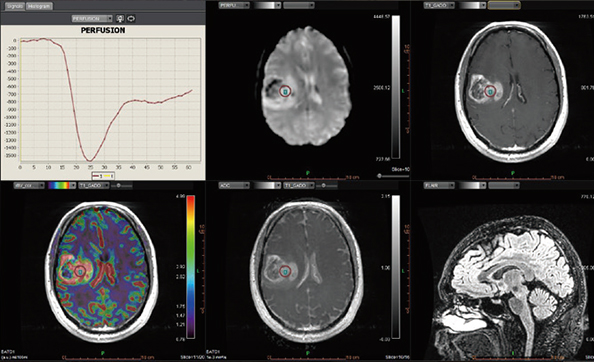

Додаток Brain Tumor Streamlined.

Додаток Brain Tumor пропонує автоматизовану покрокову обробку, включаючи кількісний мультипараметричний аналіз. Ця програма також включає оптимізований алгоритм корекції витоку контрастної речовини для підвищення точності оцінки DSC MР-перфузії.

Додаток MR Neuro

Додаток Neuro інтегрований у розширену візуалізацію Vitrea і забезпечує спеціальні протоколи для пухлини мозку та розширені протоколи інсульту, які забезпечують швидку оцінку захворювань головного мозку.

Обчислює оптимізовані параметричні карти (rBV, rBF, TTP, MTT, TMAX, tMIP) із первинної перфузійної серії

Використовує автоматизований та настроюваний робочий процес

Включає повністю автоматизовану поетапну обробку для пацієнтів з пухлинами мозку, включаючи кількісний та якісний мультипараметричний аналіз

Забезпечує корекцію витоку контрасту та створення карти K2 rBV

Пропонує один спеицифічний додаток: Розширений додаток Brain Tumor DSC DCE Expanded